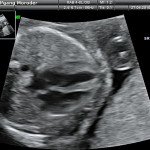

L’ecografia è una tecnica che consente di vedere gli organi del nostro corpo con l’utilizzo di onde sonore ad alta frequenza (ultrasuoni, non udibili dall’orecchio umano) che attraversano i tessuti. La sonda ecografica invia impulsi di onde sonore nel corpo. Quando le onde sonore arrivano al feto mandano degli echi: tali echi (o onde di ritorno) sono trasformati in immagini sul monitor dell’ecografo. Con l’ecografia è quindi possibile osservare in modo dettagliato il feto.

- Che cosa si vede con l’ecografia?

Nei primi mesi di gravidanza, con la misura della lunghezza del feto, è possibile valutare se lo sviluppo corrisponde all’epoca di gravidanza valutata in base alla data dell’ultima mestruazione, il numero dei feti e la presenza dell’attività cardiaca.

Dal secondo trimestre si misurano altre parti fetali, ed i valori di tali misure vengono confrontati con quelli delle curve di riferimento. Si può così valutare la normalità o meno della crescita fetale. Inoltre periodo si visualizzano la sede di inserzione placentare e la quantità di liquido amniotico.

Con l’ecografia transvaginale è possibile vedere dopo circa 3 settimane dal concepimento la camera gestazionale nella cavità uterina. Successivamente è possibile visualizzare l’embrione (3-5 mm.) a circa 6 settimane dall’ultima mestruazione (4 settimane dal concepimento) ed a questo periodo è già visibile l’attività cardiaca fetale Anche i primi dettagli sulla morfologia fetale (polo cefalico, abbozzi degli arti) sono visualizzabili più precocemente con l’ecografia transvaginale, risultando essi visibili intorno a 8-9 settimane.